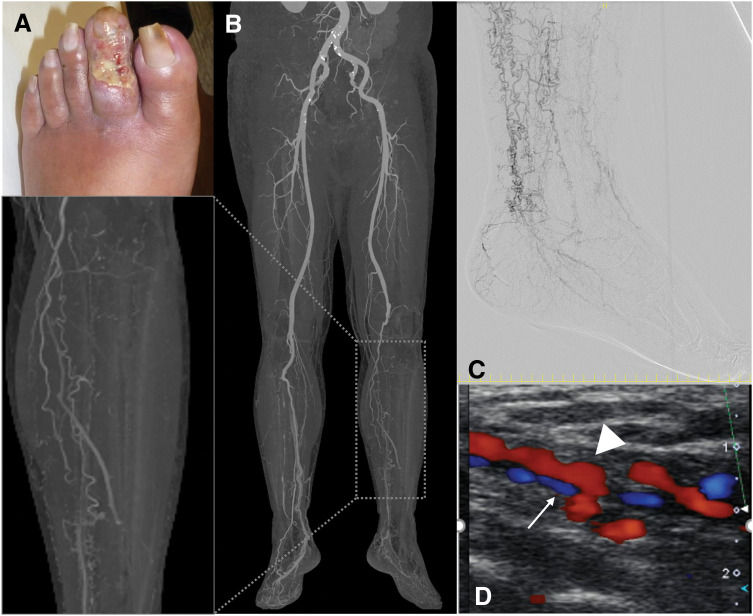

Case presentation: A 51-year-old man with a 12-year history of TAO presented with rest pain and a necrotic ulcer on the 2nd toe. He had recently ceased smoking after a 31-year history. Imaging demonstrated complete occlusion of the popliteal and tibial arteries, with foot perfusion reliant on corkscrew collaterals. The ankle-brachial index was 0.43, and skin perfusion pressure (SPP) was critically low. A severely diseased plantar artery was identified as a potential distal target. Given the high risk of graft failure, a hybrid strategy combining in situ bypass and surgical distal venous arterialization (DVA) was preoperatively planned. To mitigate perioperative vasospasm, a lumbar sympathetic block was administered 1 week prior to surgery. An in situ bypass using the ipsilateral great saphenous vein was constructed from the superficial femoral artery to the plantar artery. DVA was established via retrograde puncture of the plantar vein, balloon angioplasty for valve sites, and end-to-side anastomosis to the bypass graft. Early duplex ultrasonography revealed anastomotic stenosis at the DVA site as well as stenosis at valve sites, both of which were successfully managed with a single endovascular procedure. The toe stump healed completely within 3 months. The graft remained patent for 2 years, and SPP was preserved even after graft occlusion. Notably, graft failure coincided with DVA occlusion, suggesting its critical role in maintaining flow. At 42 months postoperatively, the patient remained ulcer-free with favorable perfusion, pain-free ambulation, and full return to work.